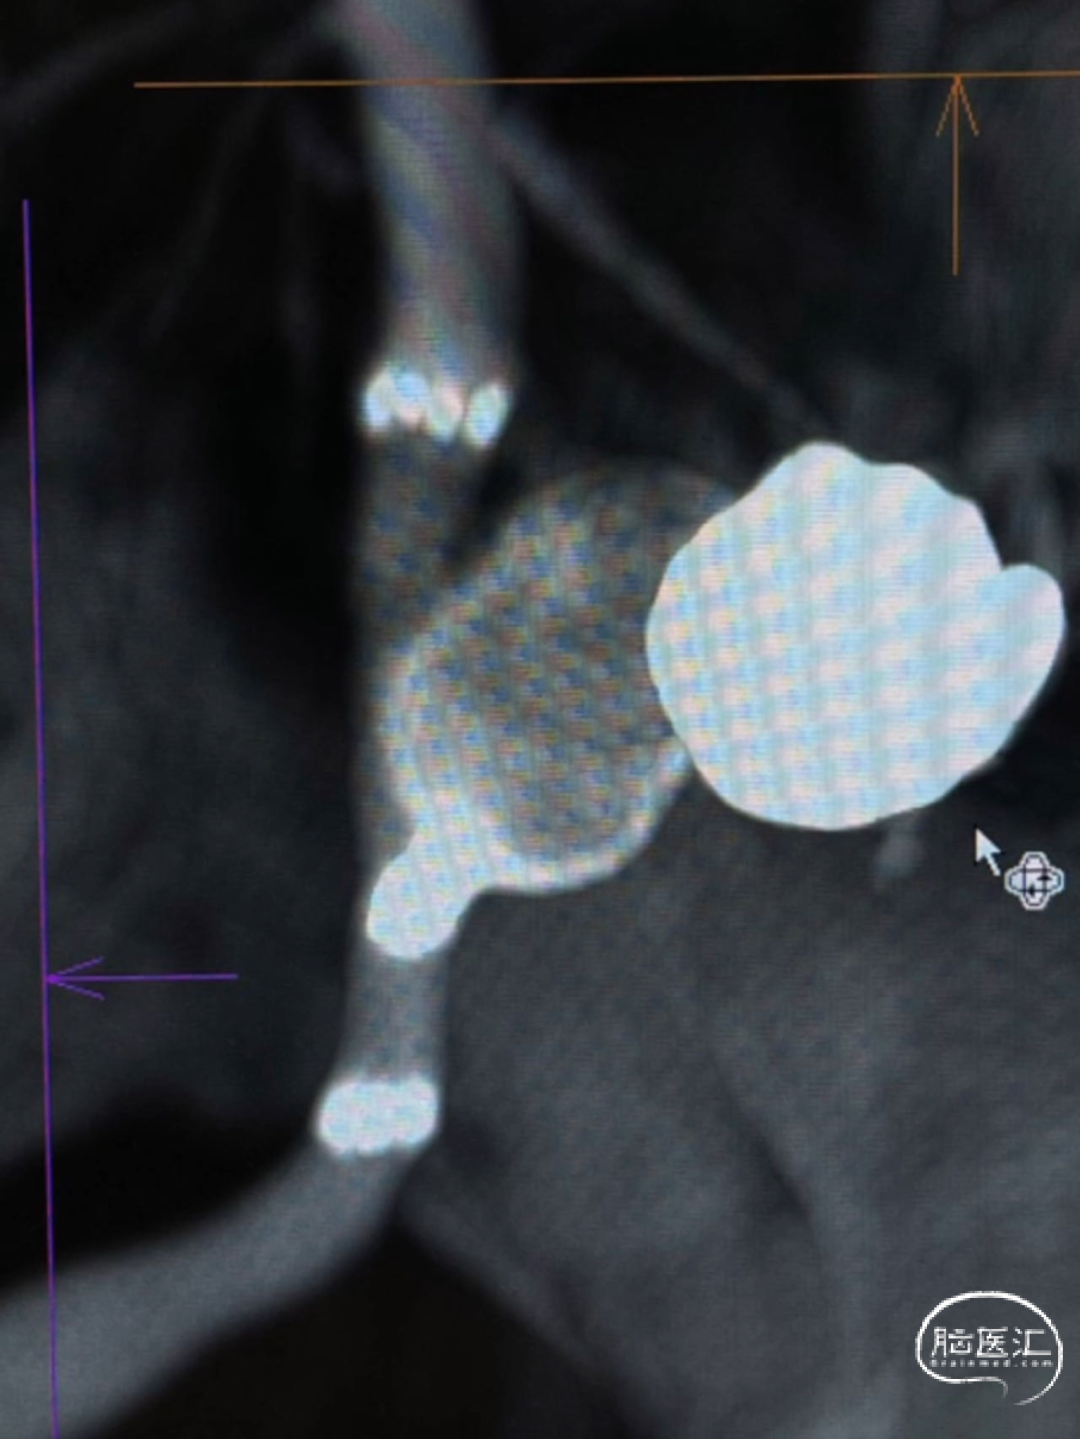

经测量可得动脉瘤宽度平均值为8.88mm,动脉瘤最小高度为7.71mm,瘤颈约为4.03mm。参考尺寸选择表,选择WEB™ SL 10*5,VIA™ 33微导管。

缓慢推出WEB™从种子至萌芽状态,继续向瘤腔内远端缓慢推送WEB™至萌芽至开花间状态;将WEB™和VIA™送至瘤顶,固定WEB™推送杆回撤VIA™,WEB™完全释放。

经造影可见WEB™尺寸合适,贴合瘤壁,小脑上动脉分支,大脑后动脉分支等血流通畅。解脱后,再次造影和Dyna-CT评估,可见动脉瘤瘤腔内有明显造影剂滞留,小脑上动脉瘤显影良好,分支血管血流正常。